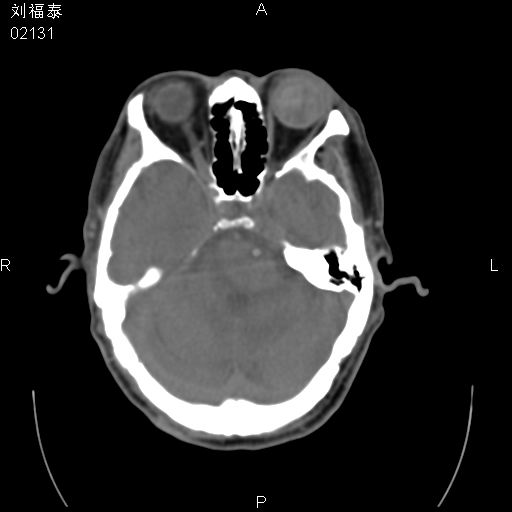

以下是引用余辉在2008-3-4 14:00:00的发言:[br]考虑左眼球黑色素瘤或血管源性肿瘤可能性大,建议增强检查

以下是引用余辉在2008-3-4 14:00:00的发言:[br]考虑眼球黑色素瘤或血管源性肿瘤可能性大,建议增强检查

以下是引用zsl6918在2008-3-4 15:08:00的发言:[br]现有征象只能提示球内出血,视网膜脱落,至于是否为肿瘤性病变需mri检查。